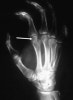

골절이나 이물확인을 위해 손의 X-ray(PA, lateral, oblique) 검사를 시행합니다.

X-ray : clenched-fit injury